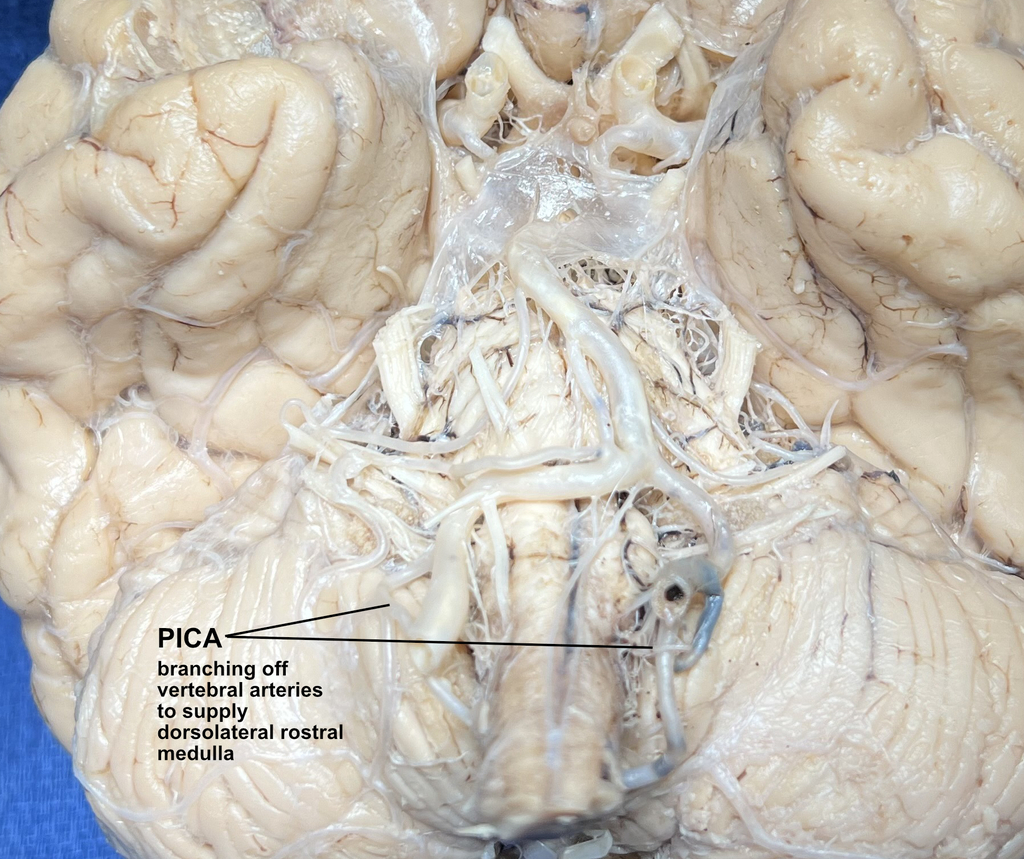

CN IX and X exit the dorsolateral rostral medulla and so it would be an occlusion of the posterior inferior cerebellar artery (PICA), not AICA, that would injure these. Also, damage to the vagus nerve would lead to hoarseness, an ipsilateral paralyzed soft palate, and dysphagia, none of which was mentioned. Select a different nerve that is more likely to be involved.